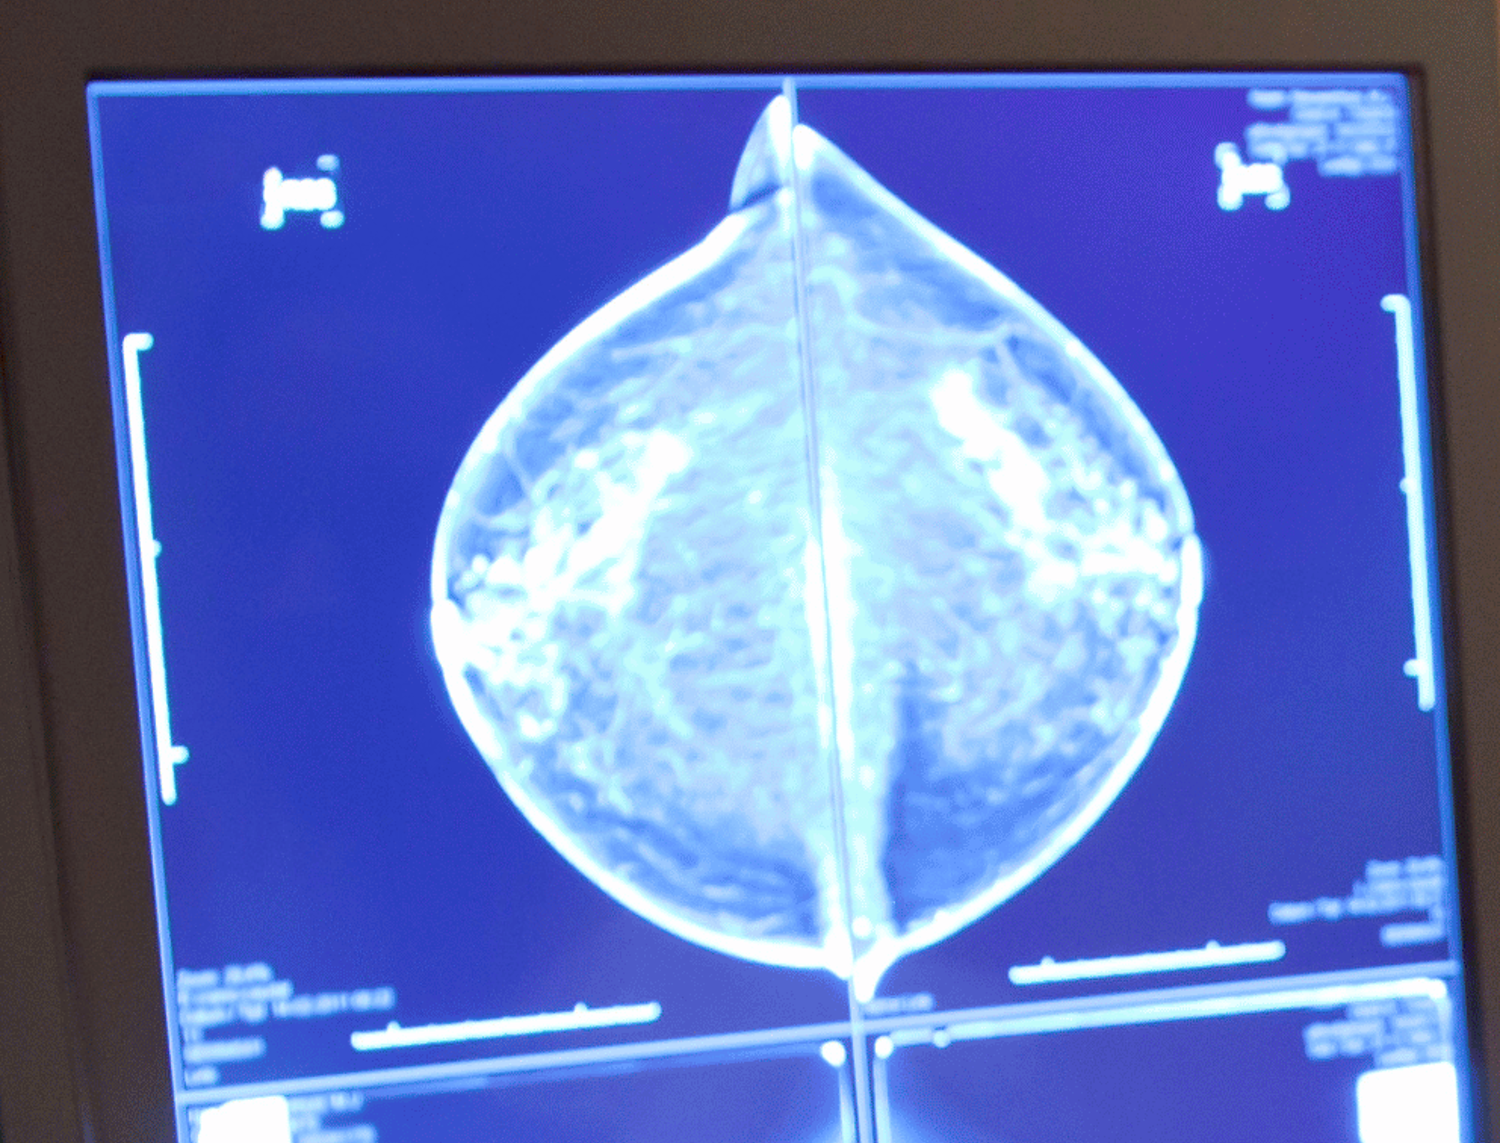

Women aged 50–74 are invited to screen every two years.

Women in their 40s and over 75 are also welcome, but we recommend you speak with your doctor first.

Screening with BreastScreen NSW is for women with no symptoms. If you notice changes in your breasts, such as a lump, pain or nipple discharge, please see your doctor as soon as possible.